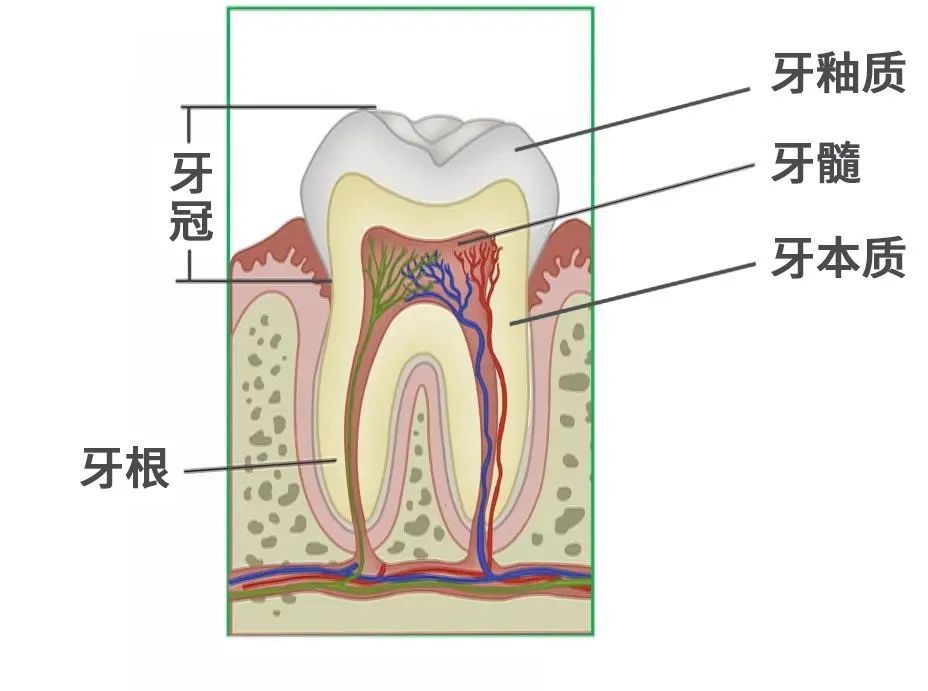

什么是显微根管治疗?

显微根管治疗是借助手术显微镜和显微器械进行,将根管系统放大,使术者能看清根管内部的结构,确认治疗的部位,在直视下进行治疗,安全高效的进行治疗,并能即刻检查治疗质量。

什么情况下需显微根管治疗?

一般来讲

对于那些牙髓炎,牙髓坏死

各种类型的根尖周炎都适于作根管治疗

包括由于龋齿、隐裂、过度消耗、穿髓等

引起的牙髓炎及牙髓坏死不能保留活髓的情况

根管治疗为什么要杀神经?

当牙髓遭受感染或不可复性损害时

如果牙髓还有部分活力

病人就会感到疼痛

为了减轻患者的症状

同时将病变牙髓清理干净

防止感染的进一步发展

就需要拔除牙髓神经

进行根管治疗

根管治疗为什么要做全冠保护?

很多病人不理解

为什么在根管治疗后

要做全冠保护

在根管治疗后

没有牙髓提供营养的牙齿会变暗、变脆

剩余的牙冠部分很容易折断劈裂

导致牙齿使用寿命减少

做全冠是对其进行保护